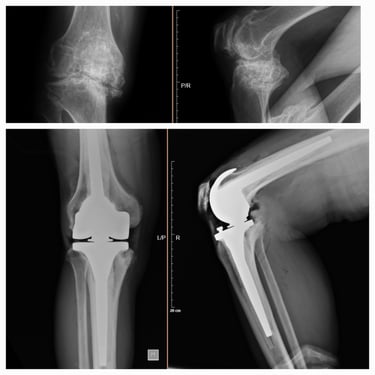

Artroplastia de rodilla (prótesis total/parcial).

Cirugía de revisión de cadera y rodilla.

Cirugía robótica de cadera y rodilla (en casos seleccionados).

Manejo de secuelas y complicaciones de prótesis de cadera y rodilla.